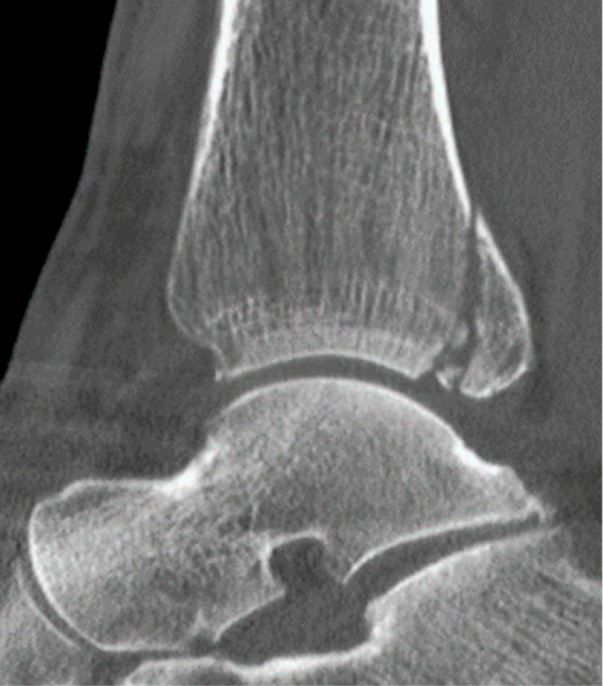

患者为83岁女性,于光滑平面滑倒后致三踝骨折,后踝为Bartonček 2型骨折,累及后外侧骨块及腓骨切迹(图2a–d)。相关合并症包括:骨量减少、软组织条件不良(皮肤呈羊皮纸样改变)、2型糖尿病(HbA1c 7.7%)。

image.png

(a)

(b)

(c)

(d)

图 2. (a–d):三踝骨折:(a) 前后位及 (b) 侧位X线片;(c) 轴位及 (d) 矢状位CT图像显示2型后踝骨折伴小中间骨块。